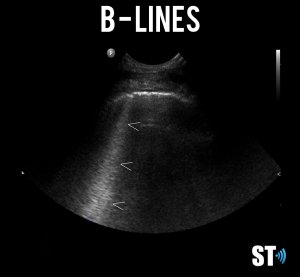

B – lines

Vertical comet-tail reverb artifacts that extend to the bottom of the screen which may be normal (1-2 per intercostal space) or indicative of alveolar interstitial fluid (3 or more B- lines in multiple locations).

This syndrome can be described as multiple B-lines in several scanning zones. In order to make the diagnosis you need at least 3 B-lines in any single intercostal space and in at least 2 zones.

B-lines